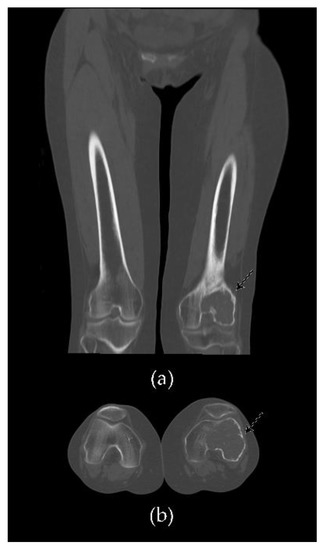

- Murphey, M.D.; Nomikos, G.C.; Flemming, D.J.; Gannon, F.H.; Temple, H.T.; Kransdorf, M.J. From the archives of the AFIP. Imaging of giant cell tumor and giant cell reparative granuloma of bone: Radiologie-pathologic correlation. Radiographics 2001, 21, 1283–1309. [Google Scholar] [CrossRef] [PubMed]

- Chakarun, C.J.; Forrester, D.M.; Gottsegen, C.J.; Patel, D.B.; White, E.A.; Matcuk, G.R. Giant cell tumor of bone: Review, mimics, and new developments in treatment. Radiographics 2013, 33, 197–211. [Google Scholar] [CrossRef]

- He, Y.; Wang, J.; Zhang, J.; Yuan, F.; Ding, X. A prospective study on predicting local recurrence of giant cell tumour of bone by evaluating preoperative imaging features of the tumour around the knee joint. Radiol. Med. 2017, 122, 546–555. [Google Scholar] [CrossRef]

- Zhou, L.; Lin, S.; Jin, H.; Zhang, Z.; Zhang, C.; Yuan, T. Preoperative CT for prediction of local recurrence after curettage of giant cell tumor of bone. J. Bone Oncol. 2021, 29, 100366. [Google Scholar] [CrossRef] [PubMed]

- Wang, C.S.; Lou, J.H.; Liao, J.S.; Ding, X.Y.; Du, L.J.; Lu, Y.; Yan, L.; Chen, K.M. Tumore osseo a cellule giganti recidivante: Caratteristiche radiologiche e fattori di rischio. Radiol. Med. 2013, 118, 456–464. [Google Scholar] [CrossRef]